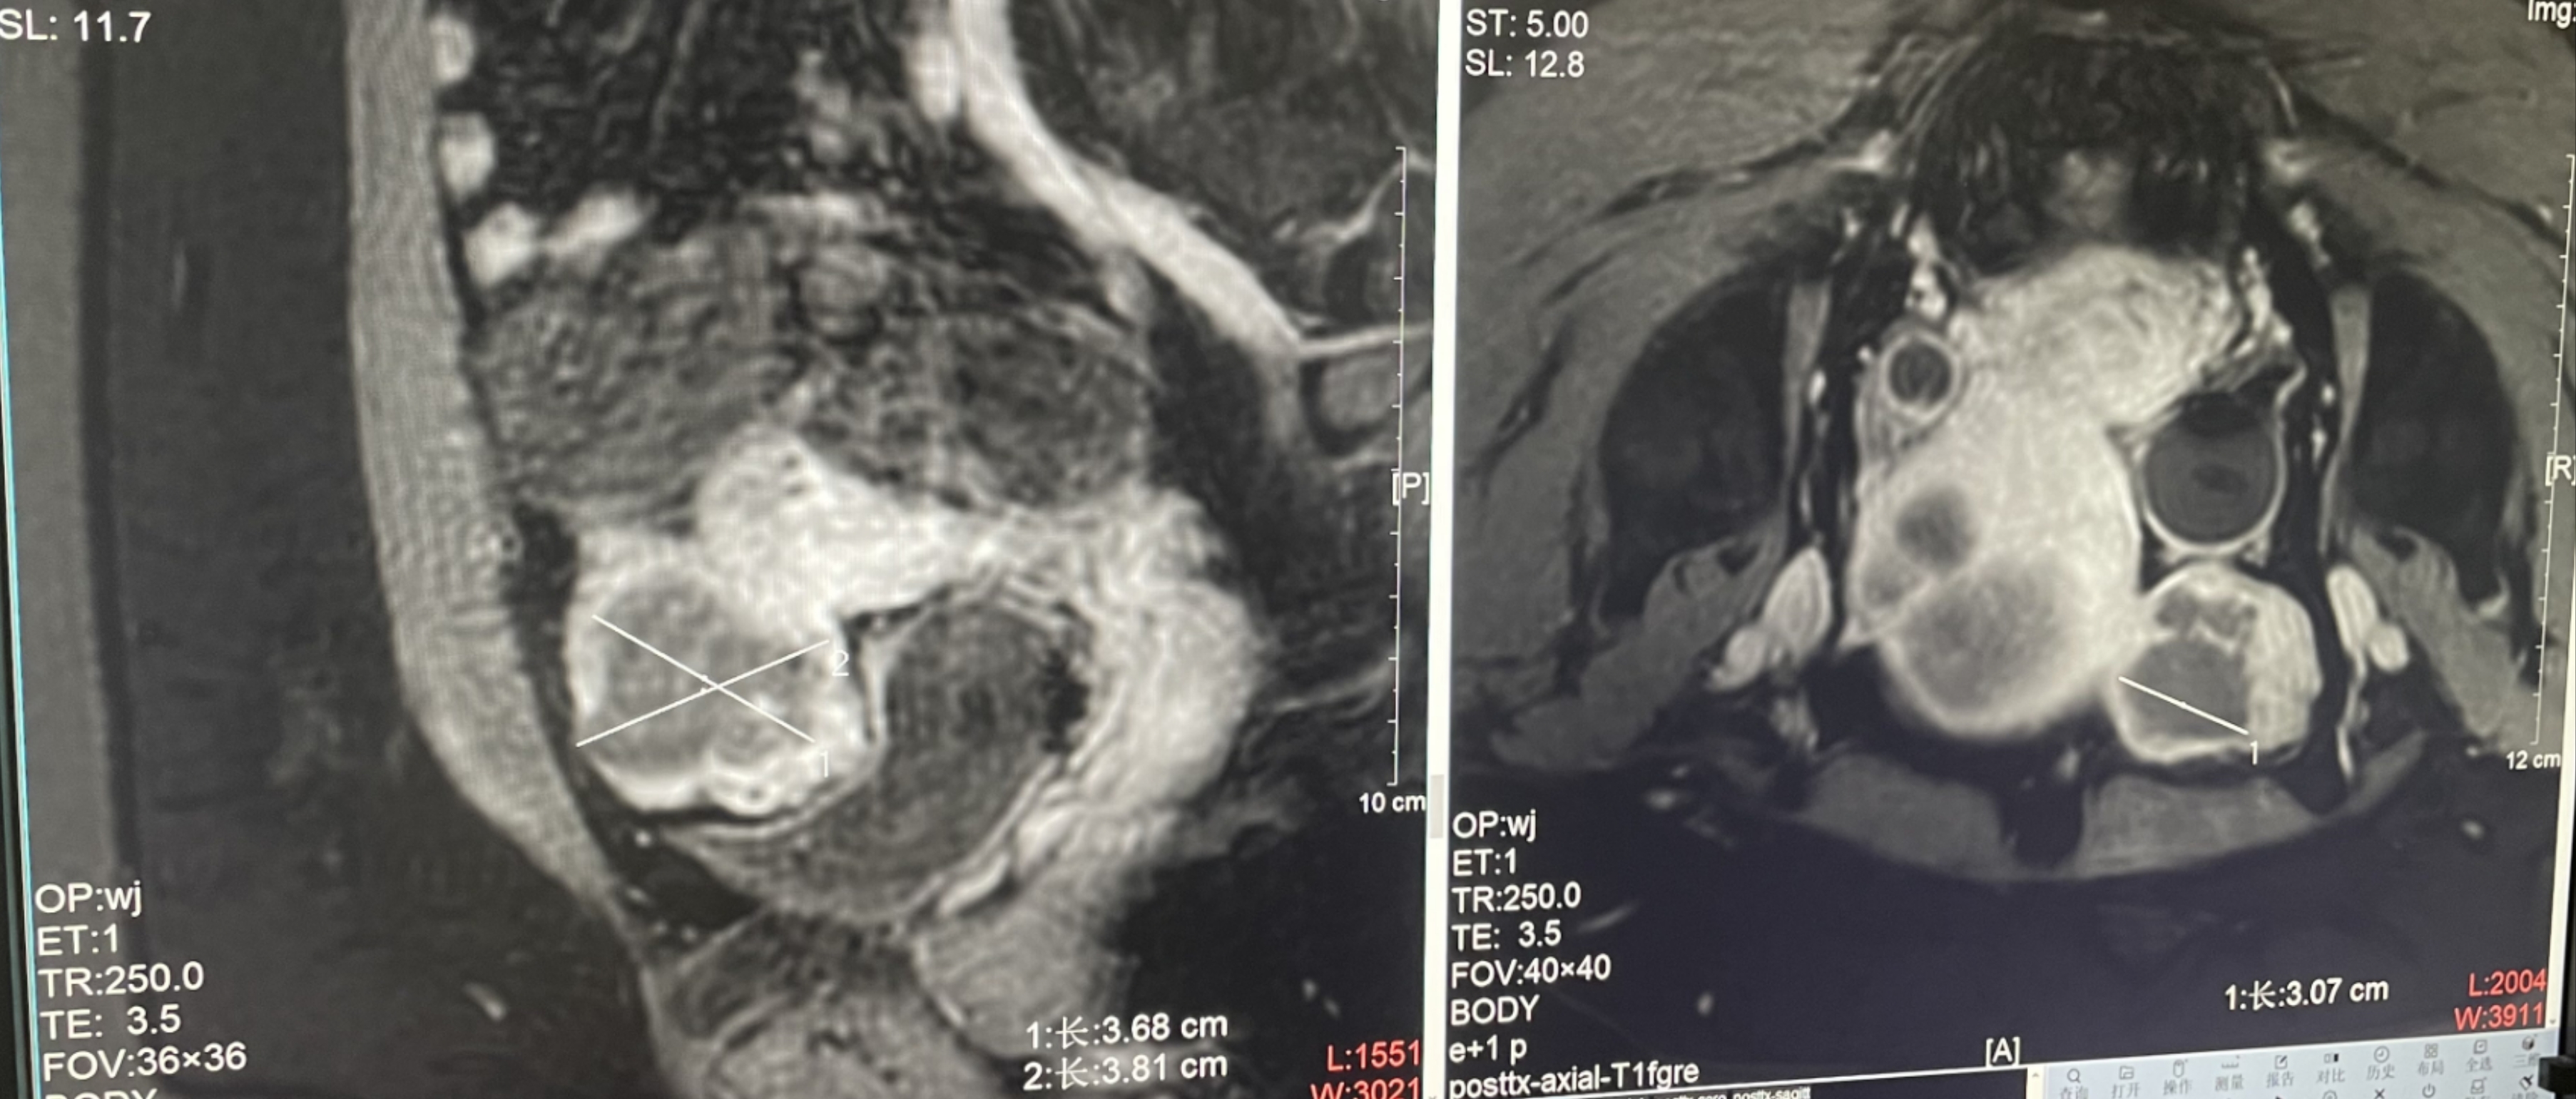

Adenomyosis

Patient Information:Female,38

Diagnosis: adenomyosis

Tumor size: about 40*37*40mm

ROT depth: The ROT center of the tumor is 45mm from the skin

Postoperative evaluation: Postoperative enhanced imaging showed a good overlap between the ablation area (right) and the lesion area (left), the non-perfusion area was continuous and consistent.

Conclusion:It has a excellent ablation effect on this lesion, and the temperature rise curve during treatment is in line with expectations. The 240CEM area of each treated target is large, full and continuous.The ablation effect was good,the NPV volume ratio was about 80.6%.